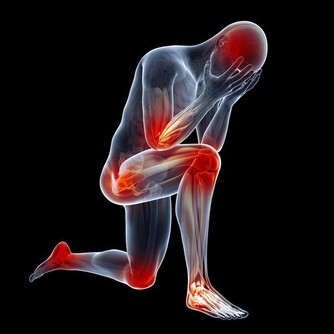

吃太飽,膨脹的胃容易使橫膈上移,影響心臟功能。而且人體為了消化吸收各種營養物質,代謝需氧量會大大增加,容易造成急性心肌缺血或心肌梗塞,引起猝死。

長期飽食使人肥胖,肥胖會引起動脈硬化、冠心病、糖尿病、癌症等一系列疾病。